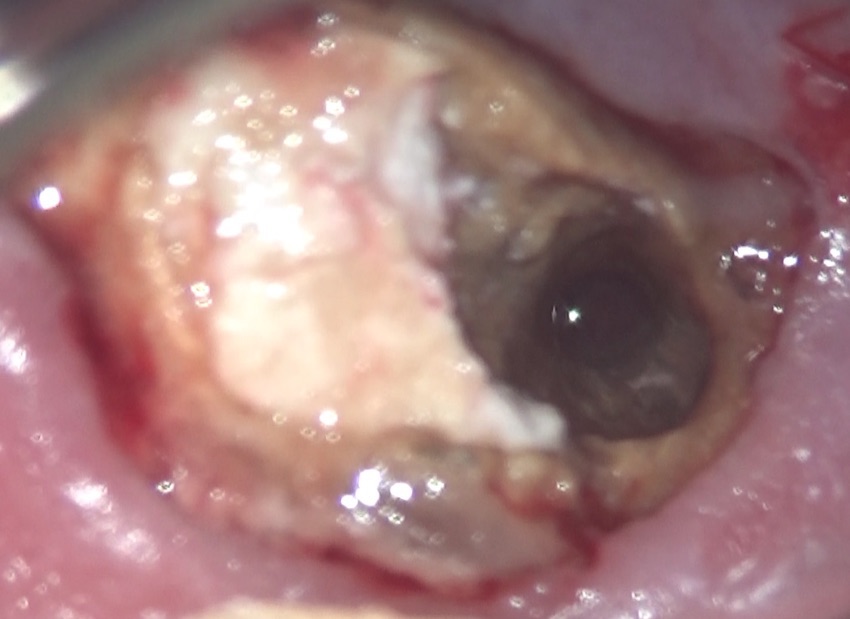

大きな穴ぼこが空いていました。

赤い→で示したのがそうです。

この歯、こんなに大きな穴が空いているのに加え、歯の残っている量が極端に少ないのです。私も、最初、抜歯です、と告げましたが、患者さんがそれでも残してくれ、というので、仕方がなく、また、もしもダメになったら、「ごめんなさい」ですからね、と伝え、治療を始めました。